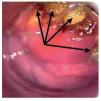

La anoscopia de alta resolución se realizó mediante la siguiente técnica: previa firma del consentimiento informado y con paciente en posición proctológica, se realizó tacto rectal para dilatación del ano, se introdujo anoscopio y se revisó el conducto anal en búsqueda de lesiones macroscópicas. Se aplicó ácido acético a 3% con un hisopo y se retiró el anoscopio. El hisopo se dejó en contacto con las paredes el conducto anal por un minuto y se retiró. Se introdujo nuevamente el anoscopio y se realizó la observación del conducto anal con microscopio de alta resolución. En los casos que se consideró necesario, a criterio del colposcopista, se utilizó la prueba de Schiling para detectar las lesiones sospechosas. Esta prueba consiste en aplicar una solución yodoyodurada de lugol a 1% o 2%, con el objeto de obtener imágenes yodo negativas (que no fijan el lugol), yodo positivas o yodo débiles (que fijan el lugol). El fundamento es que únicamente los tejidos maduros, provistos de glucógeno fijan el yodo, razón por la que el epitelio maligno o atípico es yodo negativo (Figuras 1-3). En las lesiones que resultaron dudosas para VPH o NIA se tomaron 1 o 2 biopsias de la lesión sospechosa. Previo al procedimiento, los pacientes acudieron con preparación intestinal a base de enemas de fosfato. No se administró profilaxis antibiótica y el procedimiento se realizó sin anestesia.

Figura 1. Anoscopia de alta resolución que muestra un patrón acetoblanca difuso. Se observa la línea de transición anorrectal. Por arriba de ella se observa el epitelio columnar y por debajo, el epitelio escamoso